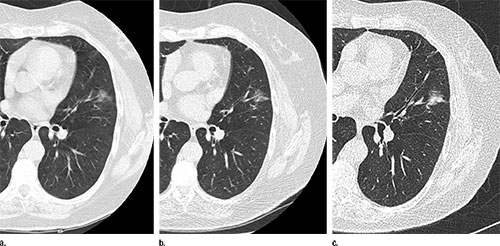

Nonsolid nodules are commonly visible on CT scans of the chest, but management of them is challenging, researchers say.

The nonsolid nodule developed a solid component—a warning sign of invasive cancer—in 22 cases prior to treatment. However, the median transition time from nonsolid to part-solid was more than two years. No cancers occurred in new nodules 15 millimeters or larger in diameter.

Findings suggest that nonsolid nodules of any size can be safely followed with low-dose CT at 12-month intervals to assess a potential transition to part-solid.